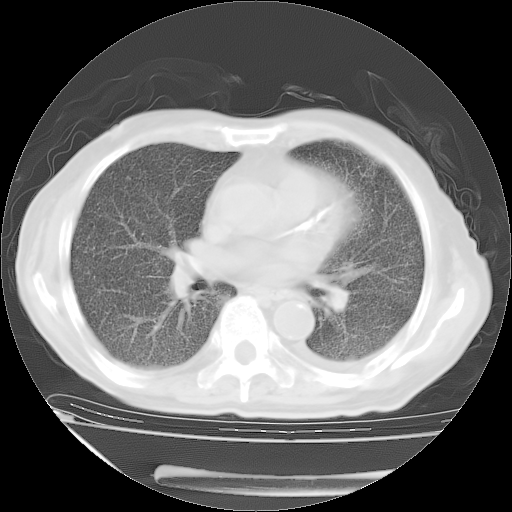

经过24天治疗,岳父的病情基本稳定。生活基本可以自理,可以下床活动。呼吸困难早已消失。体温基本正常。

主要治疗甲强龙80mg×14天,60mg×10天;同时抗结核(异烟肼+利福平+乙胺丁醇)。环磷酰胺0.1 tid 10天。

特别感谢胡教授、高管、桃子版主给出关键的治疗建议。桃版把所有肺部影像和全部临床资料请所在医院呼吸科、感染病科、结核科、临床免疫科专家会诊。临床免疫科专家制定了完整的治疗方案。